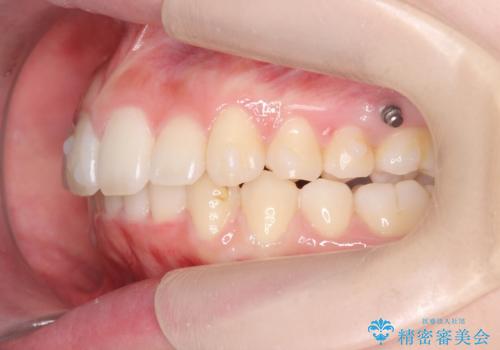

口腔内の清掃状態の良さに加えて、マウスピースを毎日きっちりと装着し、しっかりと使用していただけたことからワイヤー矯正は行わずにきれいに歯並びを治すことができました。

途中顎位が変わり、マイクロインプラントを併用した上顎臼歯の遠心移動が必要となったため治療が長期化しました。